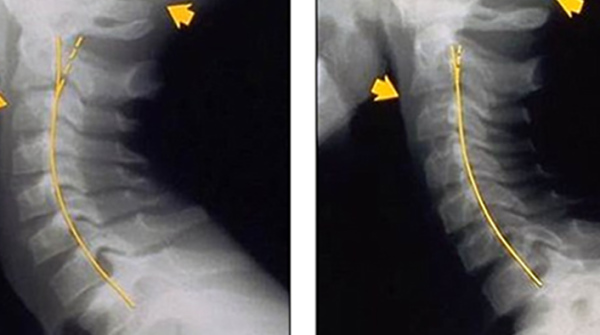

Dopodiché, come sempre in ambito scientifico, è necessario avvicinarsi con estrema cautela. Ma certo le radiografie diffuse dal chiropratico australiano James Carter di Niagara Park sono impressionanti.

Raccontano infatti, in bambini molto piccoli di 6 o 7 anni ma anche in adolescenti, una schiena a zainetto e un mutamento della postura e della colonna vertebrale che sembra quasi riportarci a quei grafici di scuola elementare in cui ci veniva spiegata,. A questo porta non staccarsi dallo smartphone (alcune statistiche parlano di quattro ore al giorno di media) e rimanere perennemente curvi, testa inclinata, sul display da cui passano ormai porzioni sempre più importanti della nostra vita.

Nessuno, ovviamente, segue le indicazioni di piazzare il telefono all’altezza degli occhi. Così Carter, già membro dell’Australian Spinal Research Foundation, esagerando ma chissà, ha lanciato l’allarme etichettando il text neck, il collo da messaggio, come una sorta di epidemia.

“Negli ultimi due anni, soprattutto nei giovani , ho visto centinaia di colli così” ha detto Carter al Daily Mail. Leggere e rispondere ai messaggini delle chat ma anche, in fondo, qualsiasi altra azione che implichi un uso dello smartphone (dal controllo compulsivo dei social network alle altre applicazioni) conduce dunque a una distribuzione errata del peso della testa sulla colonna, con il collo costretto ad arcuarsi. La gobba da tecnodipendenti è servita. Sostengono la tesi diversi altri medici interpellati dal quotidiano britannico e altri in generale.